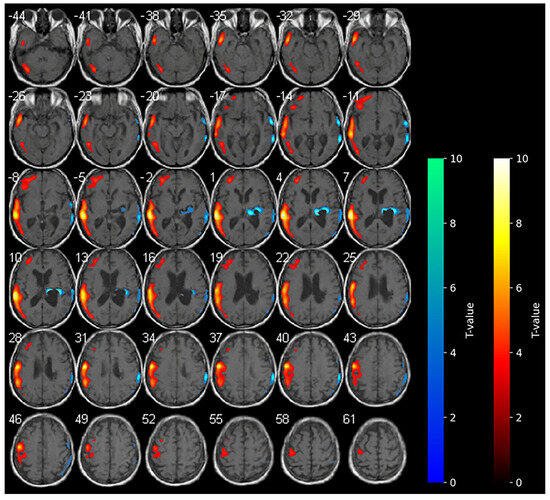

3.1. Baseline 18F-FDG-PET (T0)

At the baseline, cerebral 18F-FDG-PET documented marked hypometabolism in the right nucleo-capsular hemorrhagic lesion and reduced uptake of the tracer on the right side at the superior and middle temporal gyrus, supramarginal gyrus, cingulate gyrus, and precentral gyrus (Figure 1). At the baseline (T0–week 2), the clinical picture of the enrolled subject was characterized by marked neurological impairments (as indicated by an NIHSS score of 19 and an mRS score of 5), suggesting severe disability in daily activities. The patient exhibited a complete loss of motor function, as evidenced by an MI score of 0 in both upper and lower limbs. Furthermore, the subject displayed impaired consciousness, with the LCF scored at 5. While the subject demonstrated capacity to respond to simple commands, their performance was non-purposeful and fragmented when complex commands were issued. Gross attention to the environment was evident; however, the subject demonstrated an inability to concentrate on specific tasks. Verbalization was often confabulatory, and the memory was notably compromised, with limited capacity for the retention of new information. The subject’s behavior was deemed to be appropriate.

Figure 1. Axial slices showing the results of the SPM analysis (t-maps) at the baseline. The blue areas indicate the locations where the voxel values of the patient were significantly hypometabolic from the normal control group (p > 0.001). The brightness of the color represents the t-value.

The present findings appear to corroborate extant hypotheses concerning the effects of tDCS on patients with stroke [31], but concurrently provide new insights. In our study, we report unexpected brain metabolism in the contralateral hemisphere determined by anodal tDCS. According to the literature, during anodal-tDCS, the widespread areas of hypometabolism observed in the affected hemisphere at the baseline were significantly reduced (see Figure 1), indicating a global increase in the metabolism within the affected hemisphere. The increase in brain metabolism of the contralateral unaffected hemisphere during anodal-tDCS of the affected hemisphere is instead quite unexpected. It is possible that the stimulation of the affected hemisphere conversely modulates anatomical and functional networks activating the contralateral hemisphere [32,33]. The clinical improvements observed in our patient could be related to the reduction in hypometabolic areas in the affected hemisphere following anodal-tDCS, also suggesting the restoration of neuronal activity function in regions previously suppressed due to stroke-related damage. The unexpected increase in metabolism in the contralateral (unaffected) hemisphere may be indicative of a compensatory or network-level reorganization process, in which stimulation of the affected primary motor cortex influences functionally connected regions across hemispheres [11], thereby highlighting the distributed nature of neuroplastic responses to tDCS.